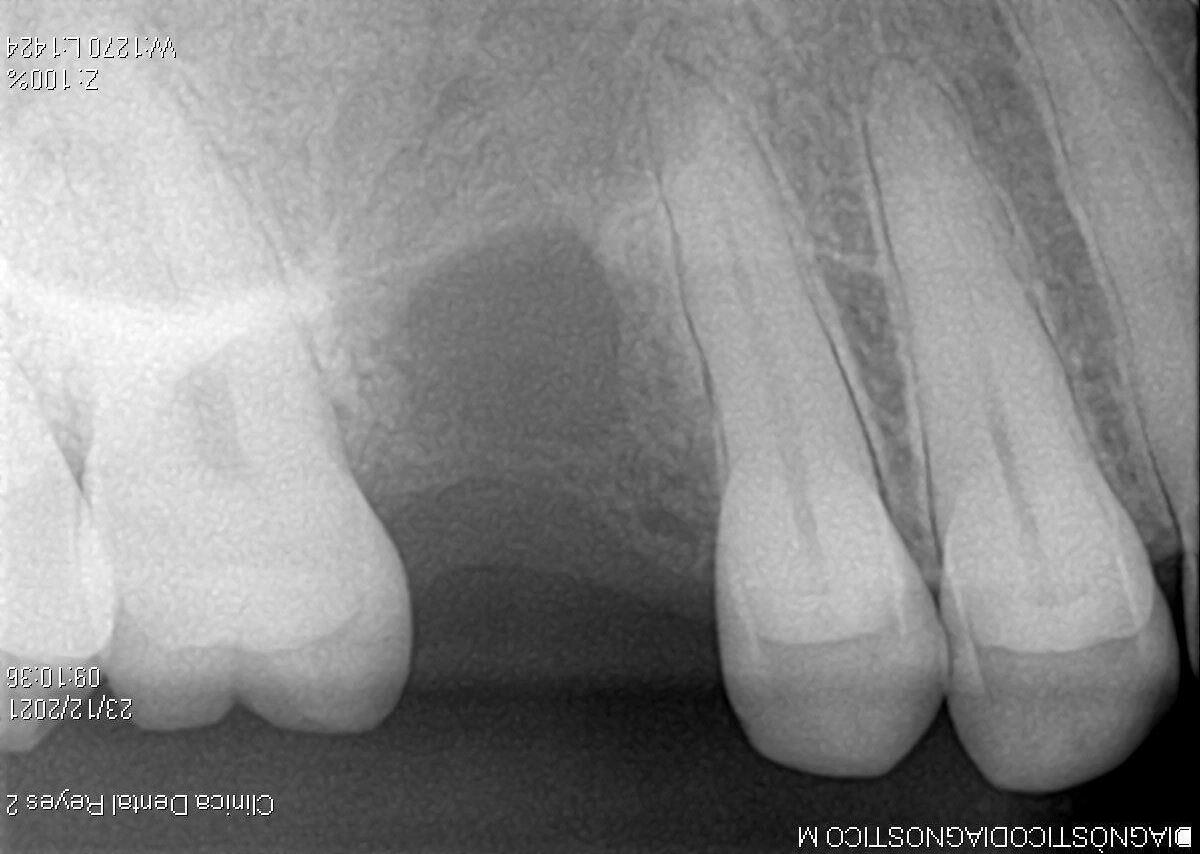

Sistémicamente sana, exámenes no reportan anomalía y radiografías presentan lesión radiolucida en cuadrante I.

Mucosa vestibular alveolar levemente con cambio de coloración, se palpa en fondo de vestíbulo masa indurada, poco dolorosa y de consistencia fibrosa.